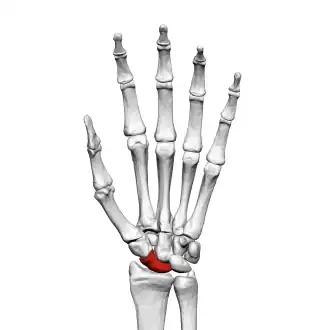

The scaphoid bone is one of the carpal bones of the wrist. It is situated between the hand and forearm on the thumb side of the wrist (also called the lateral or radial side). It forms the radial border of the carpal tunnel. The scaphoid bone is the largest bone of the proximal row of wrist bones, its long axis being from above downward, lateralward, and forward. It is approximately the size and shape of a medium cashew nut.

The scaphoid is situated between the proximal and distal rows of carpal bones. It is located on the radial side of the wrist,[1]: 176 adjacent to the styloid process of the radius.[2] It articulates with the radius, lunate, trapezoid, trapezium, and capitate.[1]: 176 Over 80% of the bone is covered in articular cartilage.[3]

The palmar surface of the scaphoid is concave, and forming a distal tubercle, giving attachment to the transverse carpal ligament. The proximal surface is triangular, smooth and convex.[3] The lateral surface is narrow and gives attachment to the radial collateral ligament. The medial surface has two facets, a flattened semi-lunar facet articulating with the lunate bone, and an inferior concave facet, articulating alongside the lunate with the head of the capitate bone.[4]